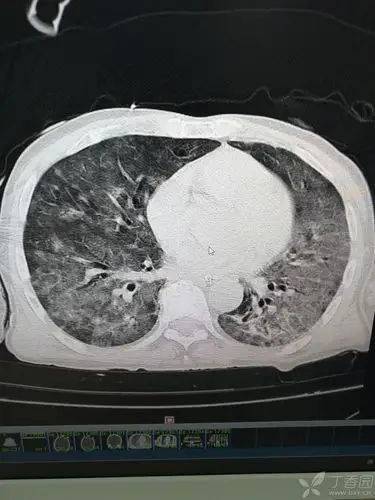

胸部ct白肺

肺部ct,求分析,尤其是第二最后一行,那个是吸气后憋气的图吧,为什么